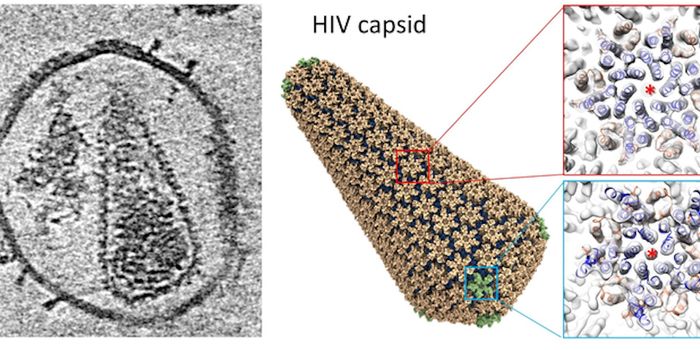

NOV 10, 2019MicrobiologyFor the first time since 2000, researchers have identified a new subtype of HIV.

FEB 02, 2016MicrobiologyUniversity of Minnesota researchers found a new, more affordable way to treat HIV. The RNA-based drug 5-azacytidin ...

DEC 15, 2018Cell & Molecular BiologyResearchers have been trying to create a vaccine for HIV, the virus that causes AIDS, for decades.